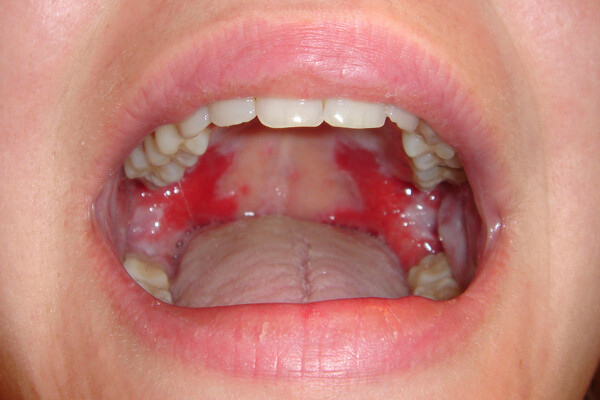

What Causes Red Spots On The Roof Of Your Mouth?

Red spots on the roof of your mouth can be caused by a variety of different reasons. Some are just a minor inconvenience, while others could be a sign of a more serious health issue that may require further investigation. Here are some common possibilities:

Canker Sores

Most people have had a canker sore at some point in their lives, and while these sores are more common on the inside of the cheeks or lips, they can occur anywhere including the roof of the mouth. Canker sores are generally a result of stress, eating particular foods, or coming in contact with other irritants. The sores normally start as small, red bumps and often develop a white center. There are over-the-counter treatments available, and most sores will heal in a week to 10 days.

Candidiasis

Also known as thrush or oral candidiasis, this fungal overgrowth can cause red bumps and white patches inside the mouth. Common in those with dentures and diabetes, candidiasis is most often treated by preventing the overgrowth in the first place. According to the ADA, oral antifungals may also be used to combat particularly tough cases. Learn more about thrush in the Colgate Oral Care resources.

Coxsackievirus

The virus behind hand, foot and mouth disease, coxsackievirus can cause painful blisters and red spots on the roof of the mouth, as well as on the hands and feet. It is most common in children under five years of age, but does occur in people of all ages. Treatment options include over-the-counter medications for fever and pain, as well as special medicated mouthwashes to help alleviate the discomfort associated with the oral sores.

In rare cases, oral sores or lesions can be a sign of oral cancer, so it is important to have any spots that are painful, cause difficulty in eating or drinking or do not heal quickly checked by your dentist.